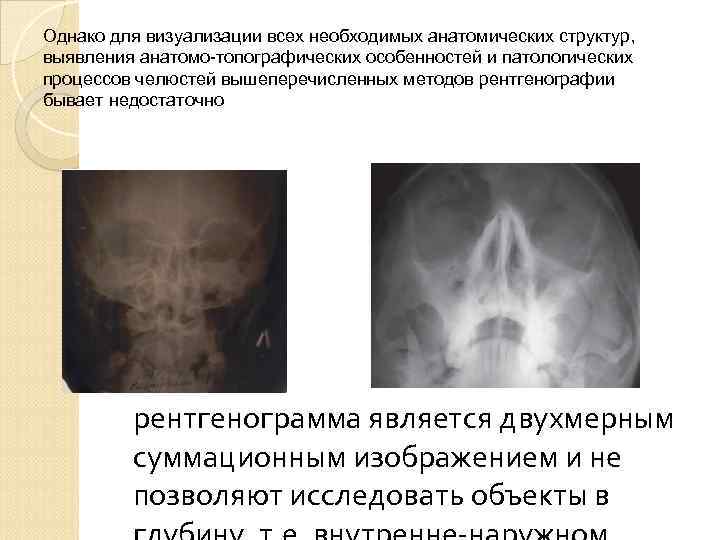

Однако для визуализации всех необходимых анатомических структур, выявления анатомо-топографических особенностей и патологических процессов челюстей вышеперечисленных методов рентгенографии бывает недостаточно рентгенограмма является двухмерным суммационным изображением и не позволяют исследовать объекты в

Однако для визуализации всех необходимых анатомических структур, выявления анатомо-топографических особенностей и патологических процессов челюстей вышеперечисленных методов рентгенографии бывает недостаточно рентгенограмма является двухмерным суммационным изображением и не позволяют исследовать объекты в

вследствие обязательных проекционных искажений, обусловленных технологией получения рентгенограмм, сложно произвести точные измерения.

вследствие обязательных проекционных искажений, обусловленных технологией получения рентгенограмм, сложно произвести точные измерения.